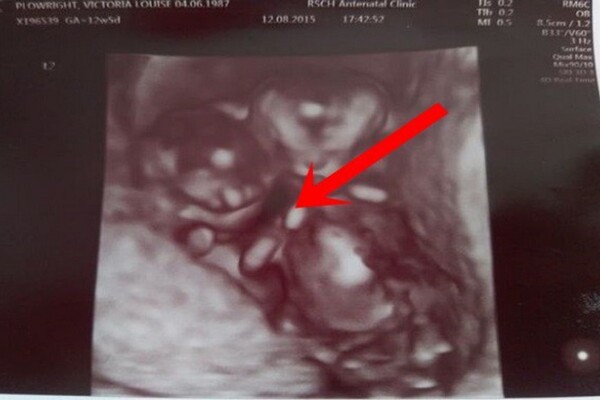

Câu chuyện của Vicky Plowright, 30 tuổi, bắt đầu khi cô phát hiện mình mang thai đôi. Thường thì các cặp song sinh cùng trứng sẽ chia sẻ nhau thai và có hai dây rốn riêng biệt, nhưng trong trường hợp này, cả hai lại nằm trong một túi ối, điều này thật hiếm gặp. Theo thống kê, trong khoảng 35.000 đến 60.000 ca sinh đôi, chỉ có một trường hợp tương tự như của Vicky. Khi bác sĩ thông báo về tình trạng này, Vicky đã cảm thấy rất sốc và lo lắng. Nguy cơ mất cả hai em bé trong bụng là khá cao, lên tới 50%.

Khi trải qua các kỳ siêu âm, các bác sĩ đã phát hiện hai em bé nằm quá gần nhau, điều này không chỉ đáng lo ngại mà còn có thể dẫn đến rối dây rốn, một tình trạng nguy hiểm có thể gây thiếu oxy cho cả hai. Mặc dù có những cảnh báo nghiêm trọng, nhưng Vicky chưa bao giờ mất niềm tin vào khả năng sống sót của hai con.

Vượt qua mọi lo lắng, sự kiên trì và tình yêu thương từ gia đình đã góp phần làm nên điều kỳ diệu. Trong những tuần theo dõi thai kỳ, các chuyên gia phát hiện ra một điều vô cùng đặc biệt: hình ảnh của hai đứa trẻ ôm chặt lấy nhau trong túi ối, hai bàn tay nhỏ nhắn nắm chặt, tạo nên một cảnh tượng ấm lòng. Chúng tự tạo ra một vị trí ổn định để ngăn chặn dây rốn bị rối, thể hiện một liên kết vô hình nhưng vô cùng mạnh mẽ giữa hai anh em.